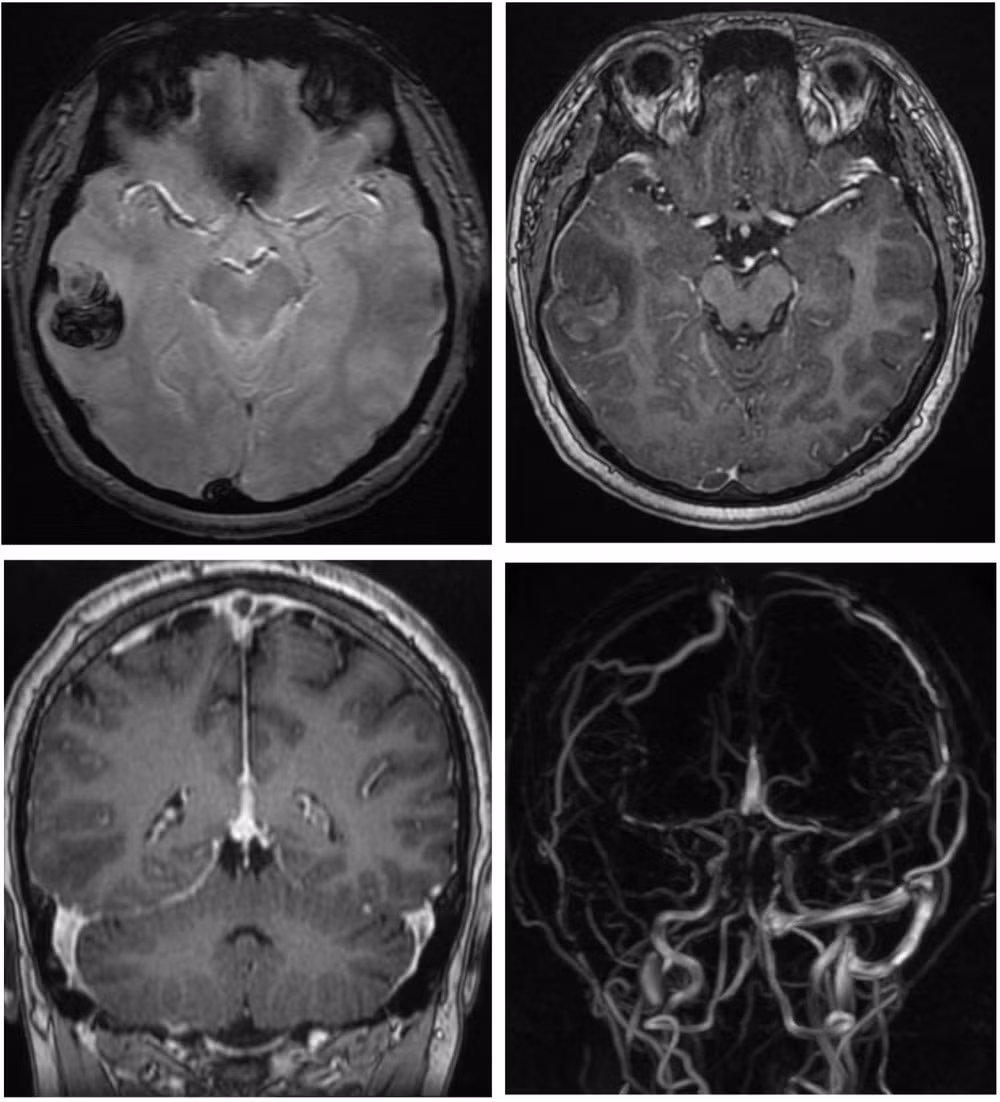

Bệnh nhân nhập viện trong tình trạng đau đầu dữ dội. Kết quả chụp CT scan cho thấy xuất huyết não, còn chụp cộng hưởng từ có bơm thuốc phát hiện huyết khối tại nhiều vị trí trong tĩnh mạch não.

Chẩn đoán hình ảnh ghi nhận bệnh nhân xuất huyết não, huyết khối nhiều vị trí trong tĩnh mạch não.